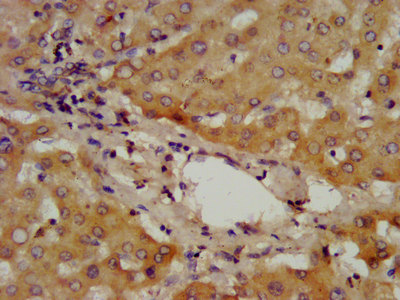

IHC image of CSB-PA001301LA01HU diluted at 1:400 and staining in paraffin-embedded human liver tissue performed on a Leica BondTM system. After dewaxing and hydration, antigen retrieval was mediated by high pressure in a citrate buffer (pH 6.0). Section was blocked with 10% normal goat serum 30min at RT. Then primary antibody (1% BSA) was incubated at 4°C overnight. The primary is detected by a biotinylated secondary antibody and visualized using an HRP conjugated SP system.